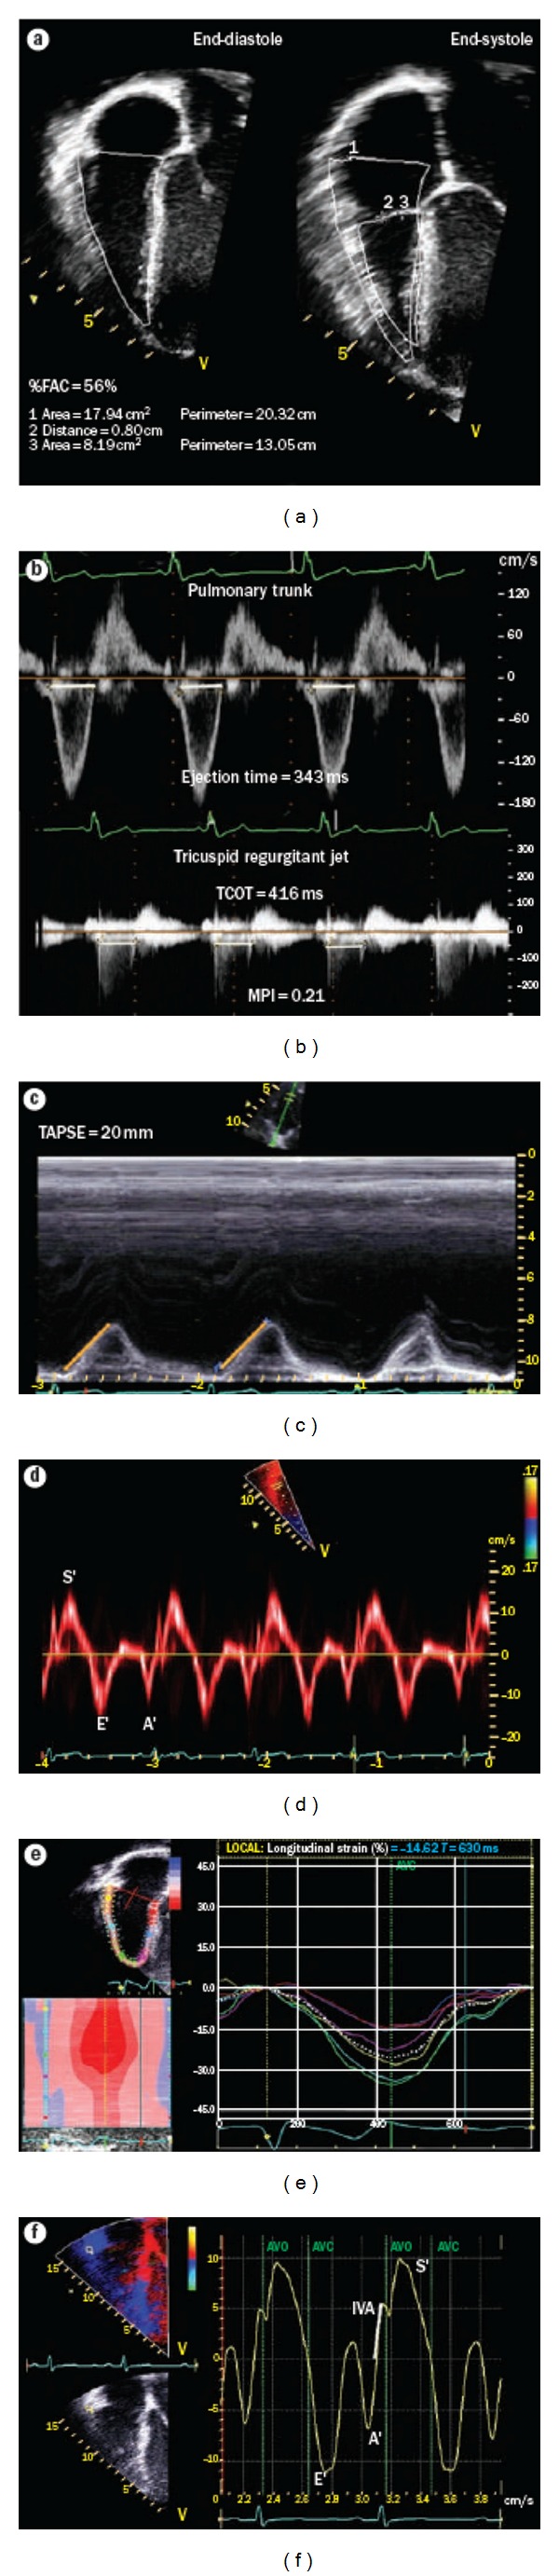

经胸超声心动图(TTE)是诊断和随访儿童和青壮年先天性心脏病(CHD)的一线工具。适当使用TTE可以减少对更多侵入性方式的需求,如心导管插入术和心脏磁共振成像。最近出现了新的超声心动图技术:组织多普勒成像,组织跟踪(应变和应变率),矢量速度成像(VVI),心肌性能指数,等容积加速(IVA)期间的心肌加速,收缩期与舒张期持续时间之比(S/D比),以及收缩期右心室(RV)功能的二维测量(如三尖瓣环平面收缩位移,TAPSE)。这些可能成为心室功能、顺应性和疾病进展的有价值的指标。此外,用于评估瓣膜功能、装置位置和心室容积的三维超声心动图正在被纳入常规临床护理。本文就这些超声心动图技术在冠心病患者中的潜在应用和局限性进行了讨论。特别关注的是超声心动图评估与右心室容量增加(如法洛四联症修复后的肺反流)或儿童和年轻人压力(如肺动脉高压)相关的右心室(RV)功能。

Transthoracic echocardiography (TTE) is the first-line tool for diagnosis and followup of pediatric and young adult patients with congenital heart disease (CHD). Appropriate use of TTE can reduce the need for more invasive modalities, such as cardiac catheterization and cardiac magnetic resonance imaging. New echocardiographic techniques have emerged more recently: tissue Doppler imaging, tissue tracking (strain and strain rate), vector velocity imaging (VVI), myocardial performance index, myocardial acceleration during isovolumic acceleration (IVA), the ratio of systolic to diastolic duration (S/D ratio), and two dimensional measurements of systolic right ventricular (RV) function (e.g., tricuspid annular plane systolic excursion, TAPSE). These may become valuable indicators of ventricular performance, compliance, and disease progression. In addition, three-dimensional (3D) echocardiography when performed for the assessment of valvular function, device position, and ventricular volumes is being integrated into routine clinical care. In this paper, the potential use and limitations of these new echocardiographic techniques in patients with CHD are discussed. A particular focus is on the echocardiographic assessment of right ventricular (RV) function in conditions associated with increased right ventricular volume (e.g., pulmonary regurgitation after tetralogy of Fallot repair) or pressure (e.g., pulmonary hypertension) in children and young adults.